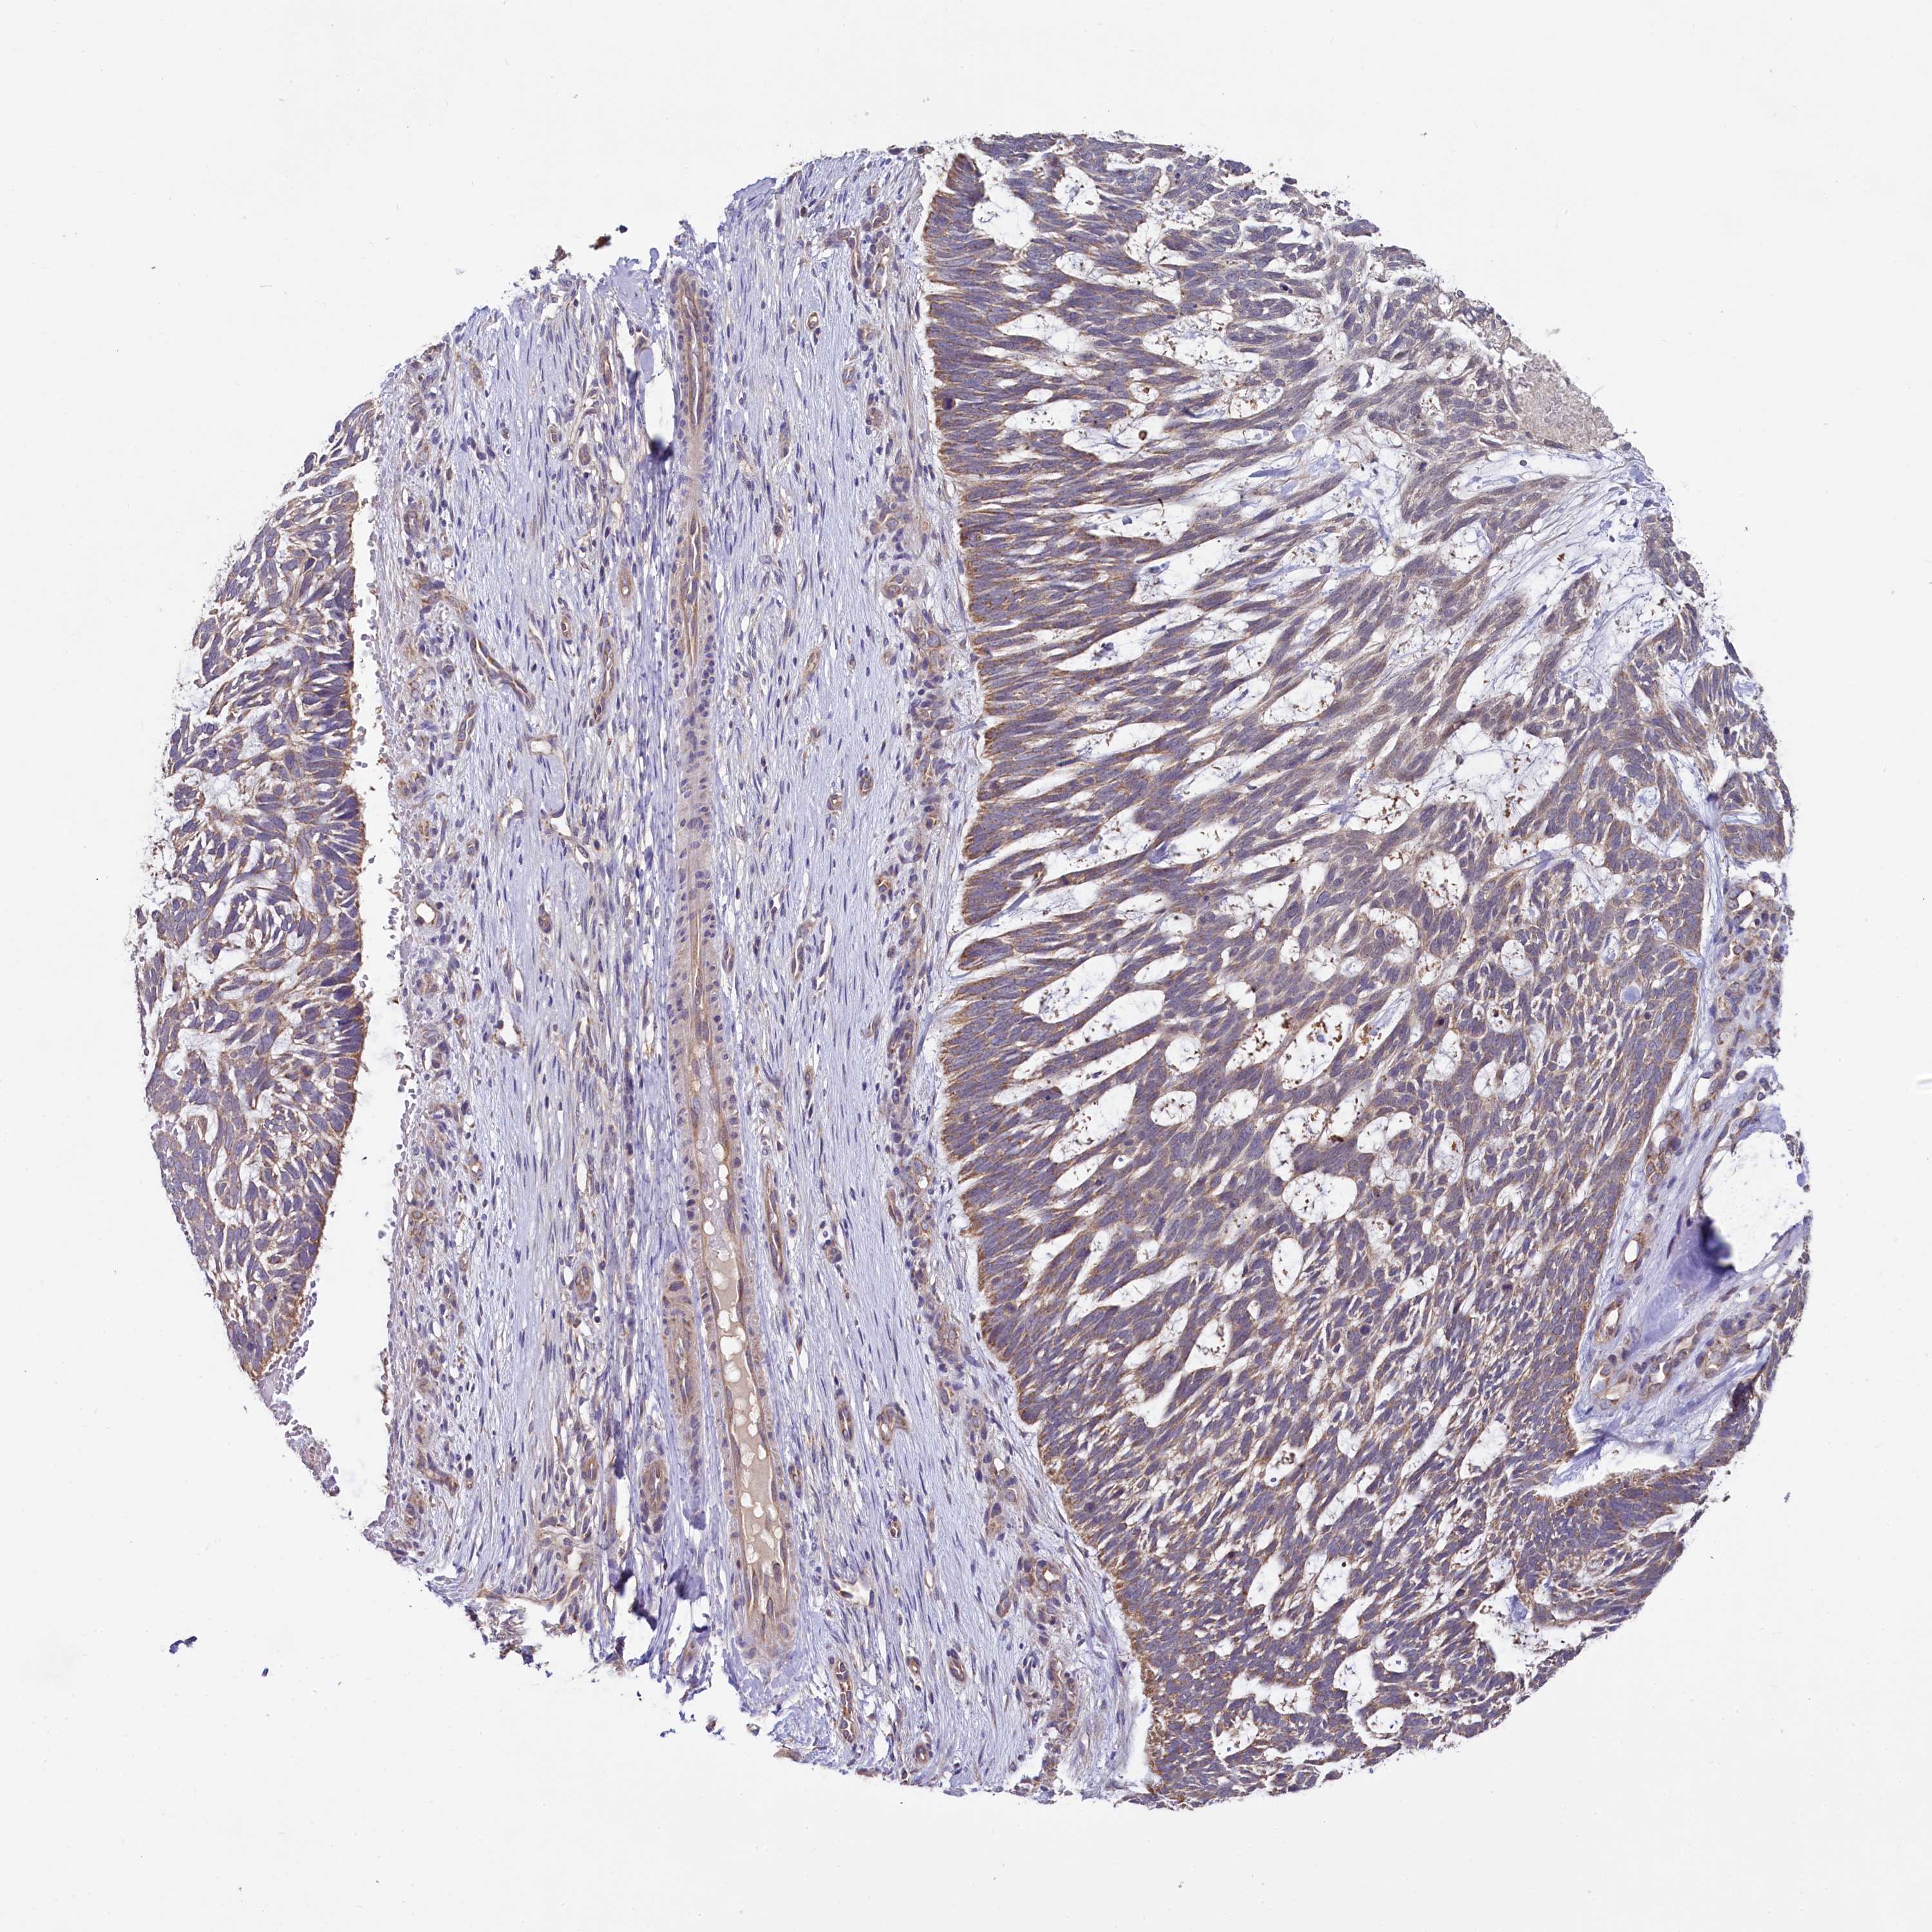

SKIN CANCER - Protein expressioni

A mouse-over function shows sample information and annotation data. Click on an image to view it in a full screen mode. Samples can be filtered based on level of antibody staining by selecting one or several of the following categories: high, medium, low and not detected. The assay and annotation is described here.

Each image is clickable and will lead to virtual microscopy that enables deeper exploration of all samples and also displays staining intensity scores, fraction scores and subcellular localization as well as patient and tissue information for each sample.

Antibody HPA039779

Squamous cell carcinoma, NOS

Squamous cell carcinoma, metastatic, NOS